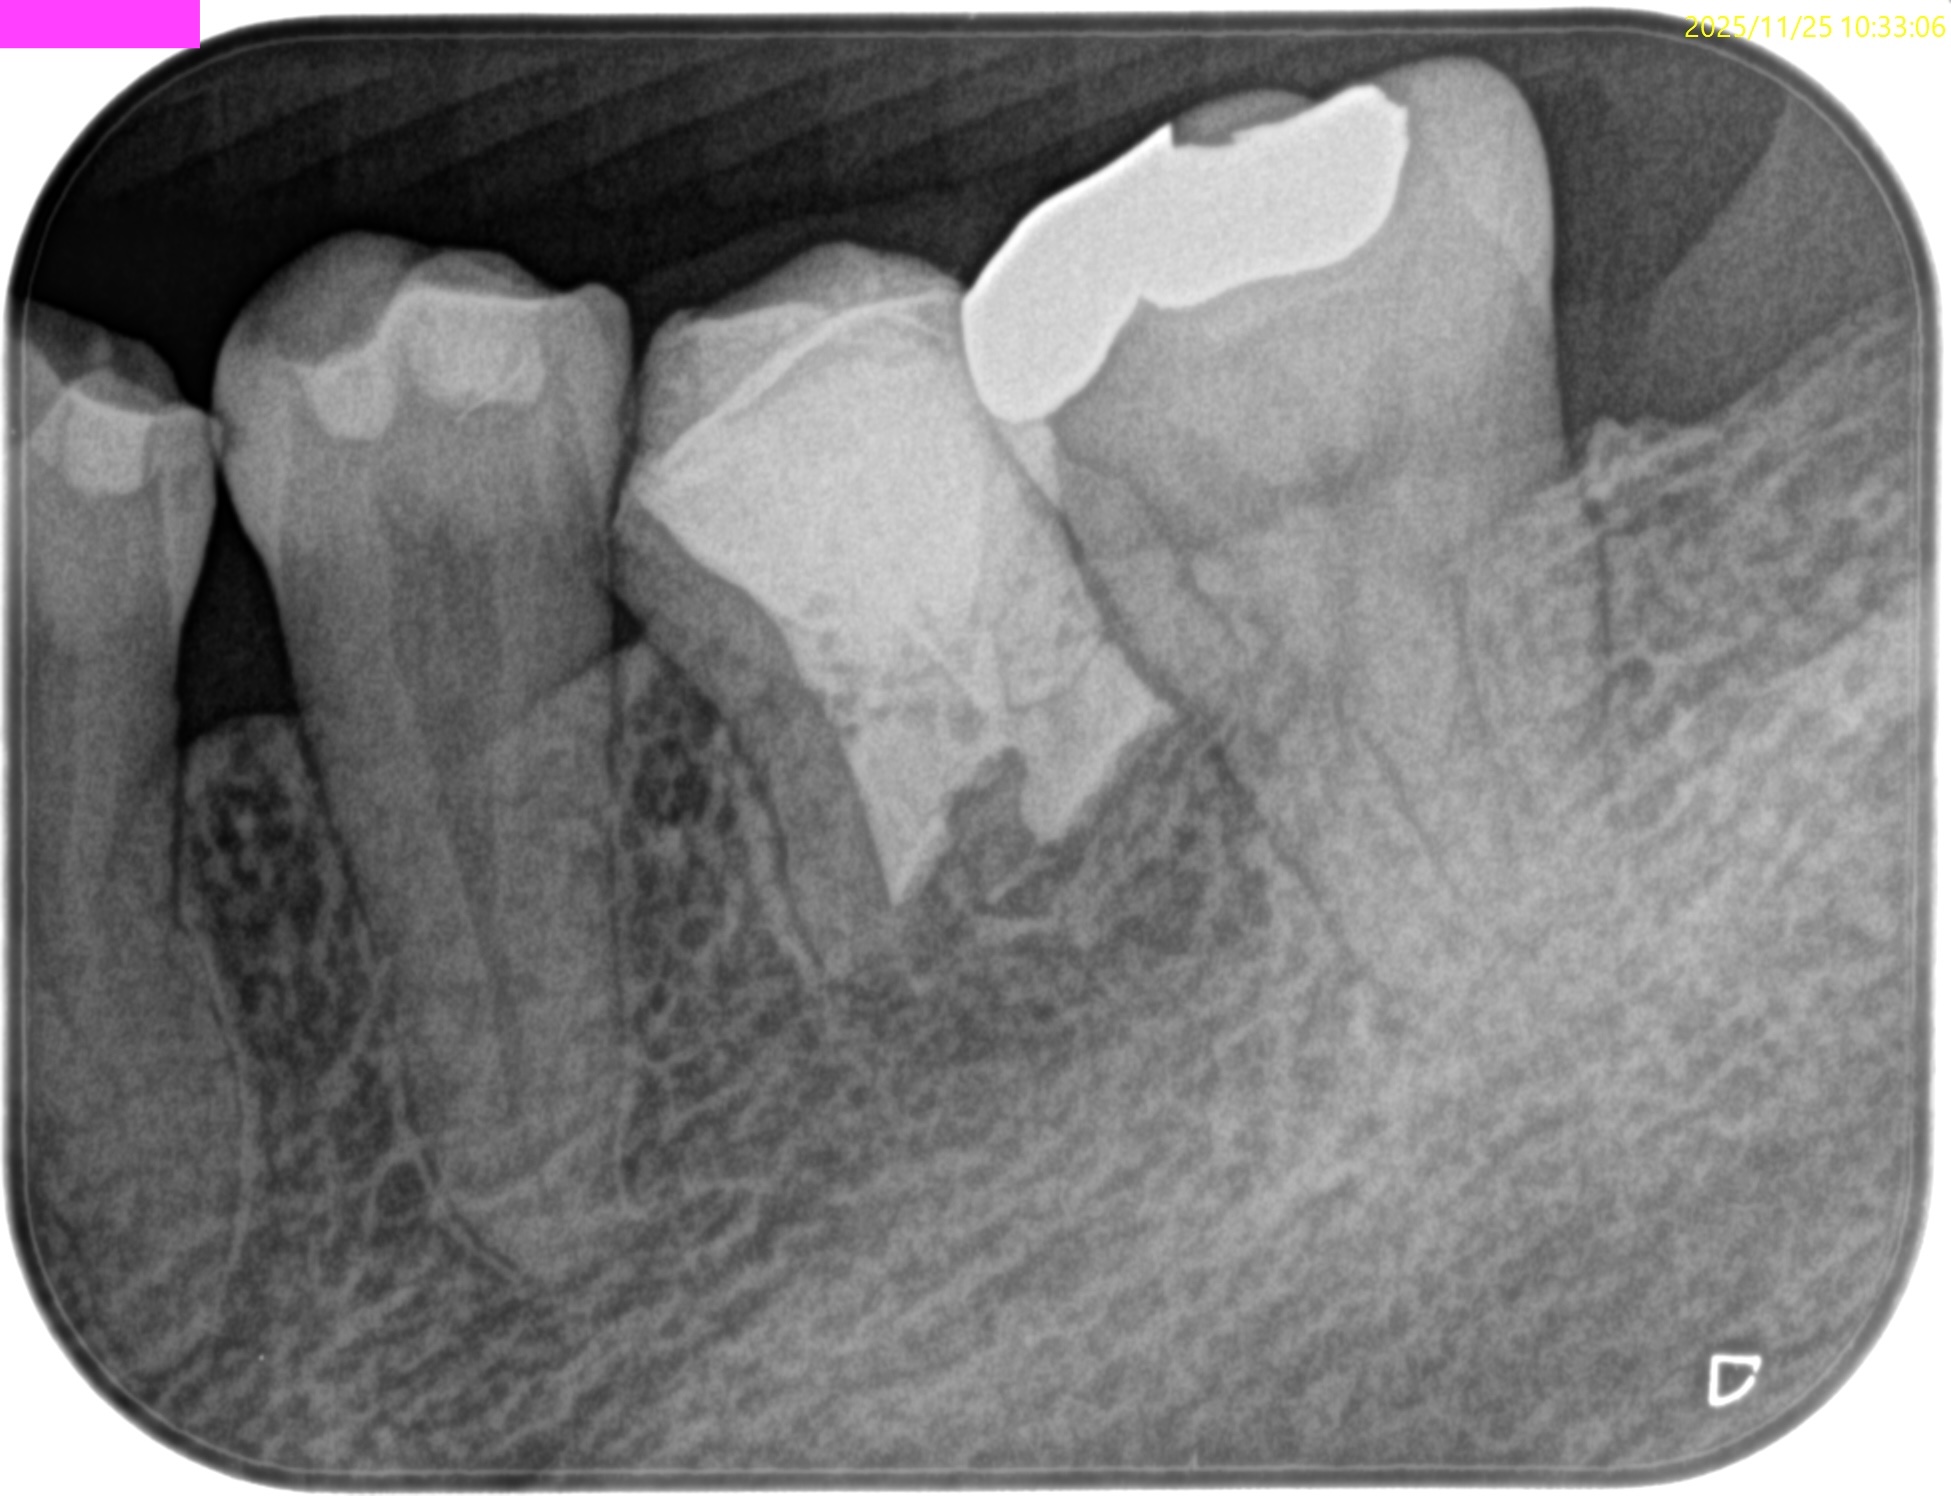

#19 M,D Apicoectomy 1yr recall(2025.11.25)

Sinus tractは

B,Lともに消失した。

M

D

術前・術直後と比較した。

90%がた治癒していると言えるだろう。